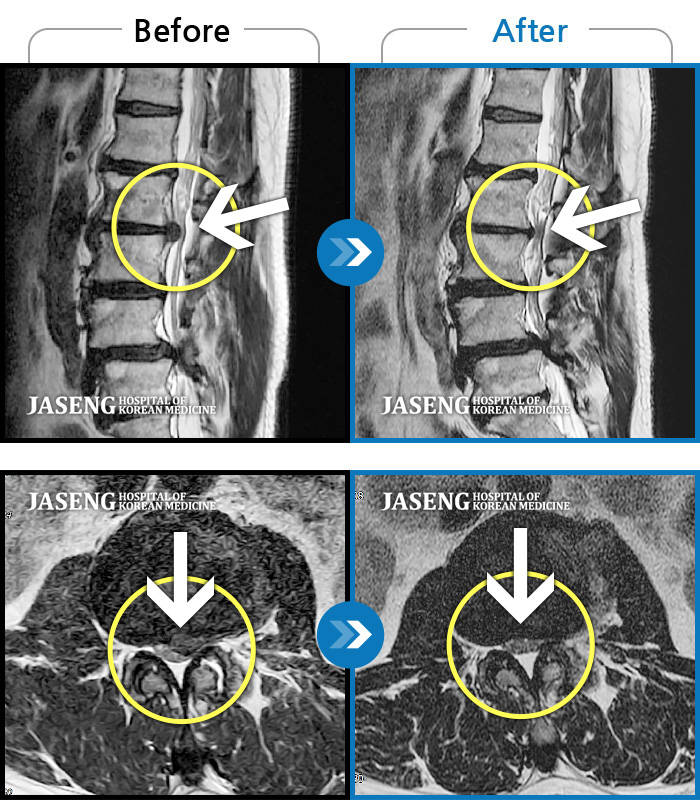

• 허리디스크